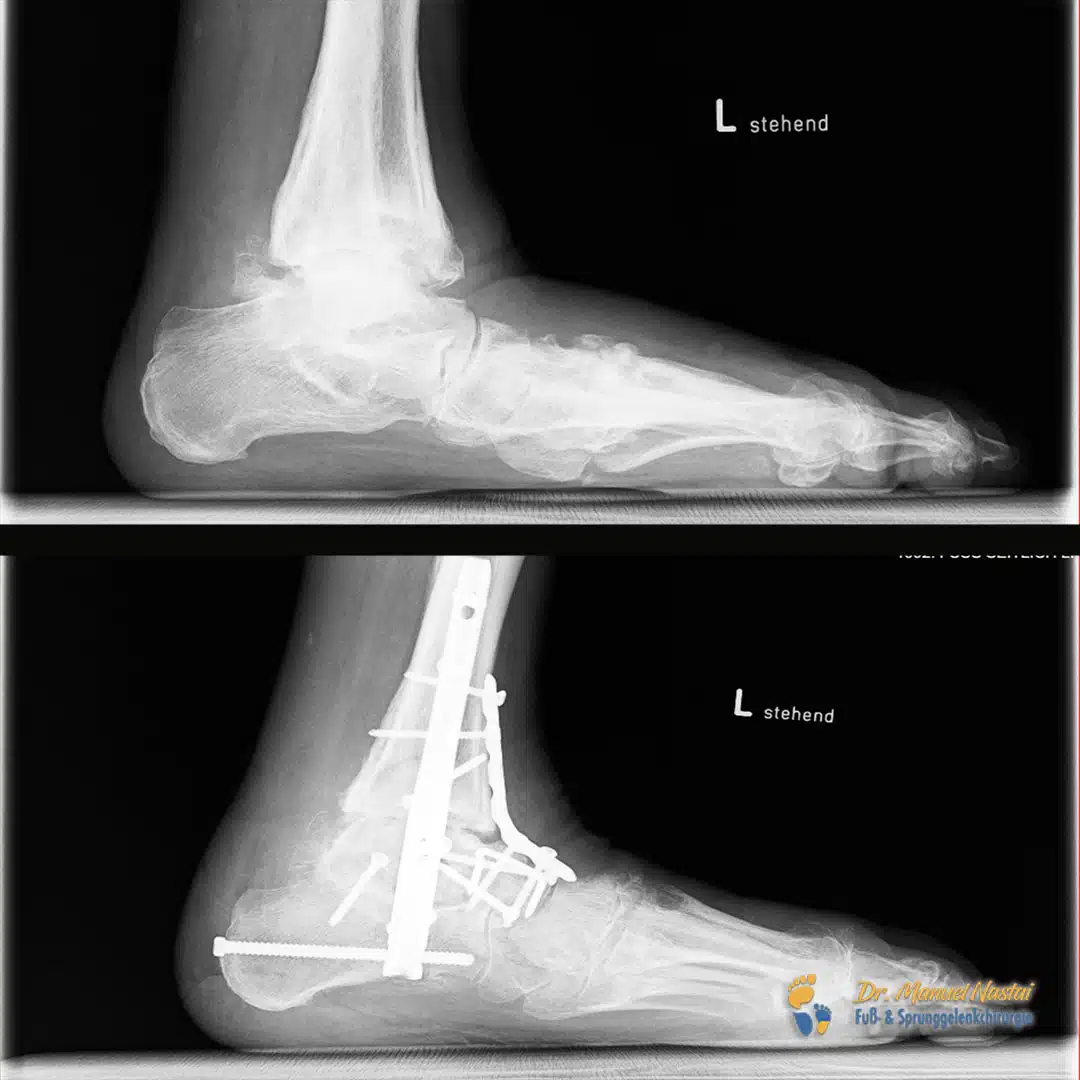

Erstes Bild Links: Seitbild: deutliche Einsenkung des Meary-Winkels (M-E-A-R-Y) = Winkel zwischen Längsachse des Talus und Längsachse des 1. Mittelfußknochens.

Normvariante/„Normalfuß“: beide Achsen verlaufen kollinear (≈ 0°).

Pathologie hier: Talus plantar abgekippt, Apex plantar → Ausdruck des Gewölbekollapses.

Zweites Bild Rechts: a.-p.-Bild: Fersenvalgus und Vorfußabduktion mit verbreiterter Auftrittsfläche.